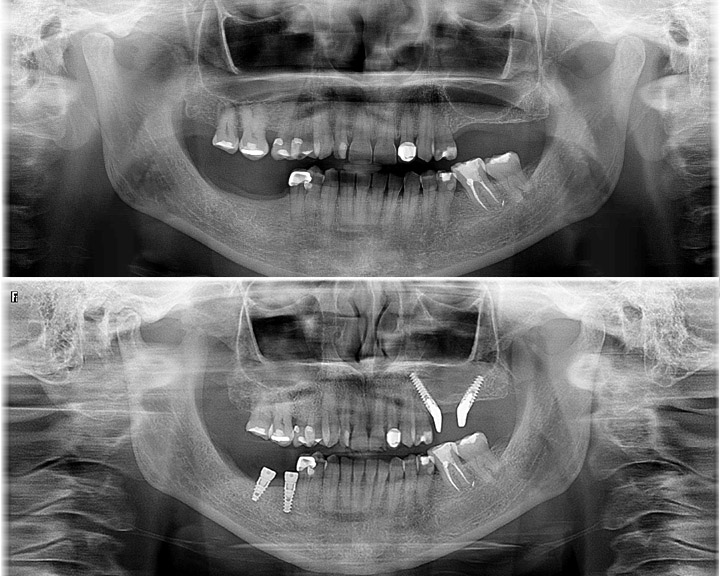

2021-07-25T10:32:01+00:00Tratamiento ortodóncico con apiñamiento dental y tendencia clase III Se presenta en nuestra clínica un caso de apiñamiento dental con tendencia clase III con pulsión lingual causante de la deformación, para su tratamiento en primer lugar realizamos el alineamiento dental con la ortodoncia mecánica de brakets además de desgaste dental interproximal (stripping dental) para ganar espacio y conseguir el alineamiento dental. Al forzar este alineamiento dental nos queda una oclusión en clase 3 que comenzamos a corregir con un aparato funcional que denominamos jumper, que empuja el maxilar superior hacia delante y la mandíbula hacia atrás hasta llegar a la posición oclusal correcta. Con [...]